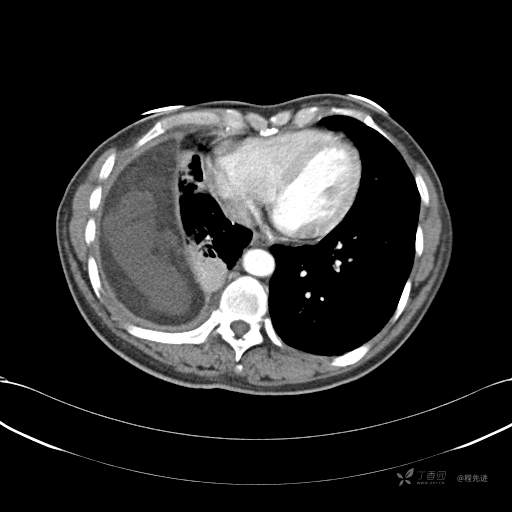

患者性别:女

患者年龄:51岁

简要病史:胸闷半年